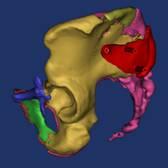

骨盆术前三维模型和模拟复位--正位前面观

模拟置钉和术后钉道

导板设计